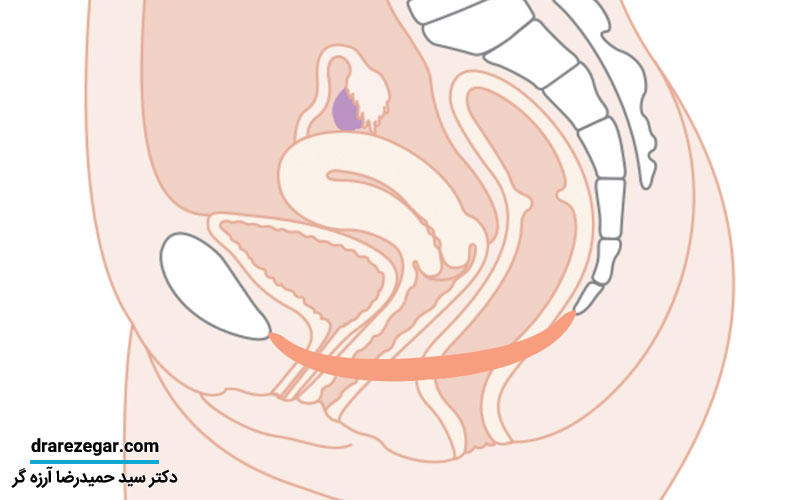

افتادگی مثانه یکی از مشکلات رایج در میان خانم ها است و زمانی اتفاق می افتد که بافت حمایتی بین مثانه و دیواره واژن تضعیف شده و دچار کشش شود. این کشیدگی که در اندام های لگنی به وجود می آید می تواند باعث ایجاد افتادگی مثانه شود که اغلب هنگام زایمان از طریق واژن یا یبوست مزمن، سرفه خشن و سخت یا بلند کردن اجسام سنگین ایجاد می شود. افتادگی مثانه می تواند در اثر یائسگی نیز به وجود آید؛ زیرا سطح استروژن کاهش پیدا می کند. معمولاً برای افتادگی های متوسط یا ملایم نیاز به درمان جراحی نیست و اغلب با درمان های دیگر برطرف خواهند شد. اما در موارد شدیدتر لازم است عمل جراحی انجام شود تا اندام ها به موقعیت مناسب برگردند. در این مقاله از سایت دکتر سید حمیدرضا آرزه گر به شما خواهیم گفت که چگونه از افتادگی مثانه پیشگیری کنید.

در کف لگن یکسری عضلات، رباط ها و بافت های اتصالی وجود دارد که می تواند از مثانه و سایر اعضای موجود در لگن حمایت کند. در اثر آسیب های زایمانی یا فشار مزمن در عضلات کف لگن ارتباط بین عضلات کف لگن و رباط ها در طول زمان تضعیف می شود و زمانی که چنین اتفاقی رخ دهد، مثانه بیشتر از حد طبیعی پایین می آید و به سمت مهبل کشیده خواهد شد. برای افتادگی مثانه می توان علل احتمالی زیر را بیان کرد:

شدت افتادگی مثانه در بیماران مختلف متفاوت است. به همین خاطر پزشک برای انتخاب بهترین روش درمانی باید نسبت به درجه افتادگی مثانه تصمیم گیری کند. افتادگی مثانه درجه ۱ یعنی مثانه به میزان کمی در نزدیکی واژن قرار می گیرد. این درجه از افتادگی مثانه جزو مراحل ابتدایی بیماری محسوب می شود. درجه ۲ نیز به صورت حرکت زیاد مثانه به سمت پایین است که در ورودی مجرای واژن قرار می گیرد. اما درجه ۳ حالت شدید عارضه بوده که مثانه از مجرای واژن کاملاً بیرون آمده است.

چنانچه بیمار دچار علایم ناراحت کننده و قابل توجهی بود، بهترین درمان انجام عمل جراحی مثانه است. در طی این جراحی مثانه جابجا شده و به محل خود باز می گردد. همچنین هدف دیگر از این عمل از بین بردن بافت اضافی و سفت کردن ماهیچه ها و رباط های کف لگن است. برای این کار ممکن است پزشک از نوع خاصی از پیوند بافت جهت بازسازی بافت واژن استفاده کند تا بتواند زمینه تقویت آن را فراهم کند. اگر بیمار تصمیم به بارداری داشته باشد، معمولاً عمل جراحی تا به بعد از زایمان موکول می شود و می توان در این زمان با استفاده از پساری علائم بیمار را کاهش داد. مهم ترین مزیت عمل جراحی این است که در سالیان طولانی بیماران بدون هیچگونه علایم و مشکلی می توانند به فعالیت های روزمره خود برسند.